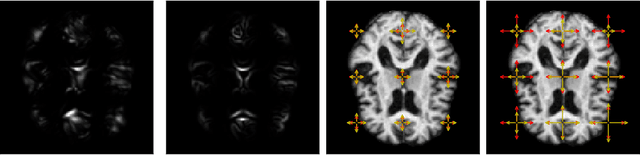

Abstract:We introduce a stochastic model of diffeomorphisms, whose action on a variety of data types descends to stochastic evolution of shapes, images and landmarks. The stochasticity is introduced in the vector field which transports the data in the Large Deformation Diffeomorphic Metric Mapping (LDDMM) framework for shape analysis and image registration. The stochasticity thereby models errors or uncertainties of the flow in following the prescribed deformation velocity. The approach is illustrated in the example of finite dimensional landmark manifolds, whose stochastic evolution is studied both via the Fokker-Planck equation and by numerical simulations. We derive two approaches for inferring parameters of the stochastic model from landmark configurations observed at discrete time points. The first of the two approaches matches moments of the Fokker-Planck equation to sample moments of the data, while the second approach employs an Expectation-Maximisation based algorithm using a Monte Carlo bridge sampling scheme to optimise the data likelihood. We derive and numerically test the ability of the two approaches to infer the spatial correlation length of the underlying noise.

Abstract:We present a framework for shape matching in computational anatomy allowing users control of the degree to which the matching is diffeomorphic. This control is given as a function defined over the image and parameterises the template deformation. By modelling localised template deformation we have a mathematical description of growth only in specified parts of an image. The location can either be specified from prior knowledge of the growth location or learned from data. For simplicity, we consider landmark matching and infer the distribution of a finite dimensional parameterisation of the control via Markov chain Monte Carlo. Preliminary numerical results are shown and future paths of investigation are laid out. Well-posedness of this new problem is studied together with an analysis of the associated geodesic equations.

Abstract:Stochastically evolving geometric systems are studied in geometric mechanics for modelling turbulence parts of multi-scale fluid flows and in shape analysis for stochastic evolutions of shapes of e.g. human organs. Recently introduced models involve stochastic differential equations that govern the dynamics of a diffusion process $X$. In applications $X$ is only partially observed at times $0$ and $T>0$. Conditional on these observations, interest lies in inferring parameters in the dynamics of the diffusion and reconstructing the path $(X_t,\, t\in [0,T])$. The latter problem is known as bridge simulation. We develop a general scheme for bridge sampling in the case of finite dimensional systems of shape landmarks and singular solutions in fluid dynamics. This scheme allows for subsequent statistical inference of properties of the fluid flow or the evolution of observed shapes. It covers stochastic landmark models for which no suitable simulation method has been proposed in the literature, that removes restrictions of earlier approaches, improves the handling of the nonlinearity of the configuration space leading to more effective sampling schemes and allows to generalise the common inexact matching scheme to the stochastic setting.